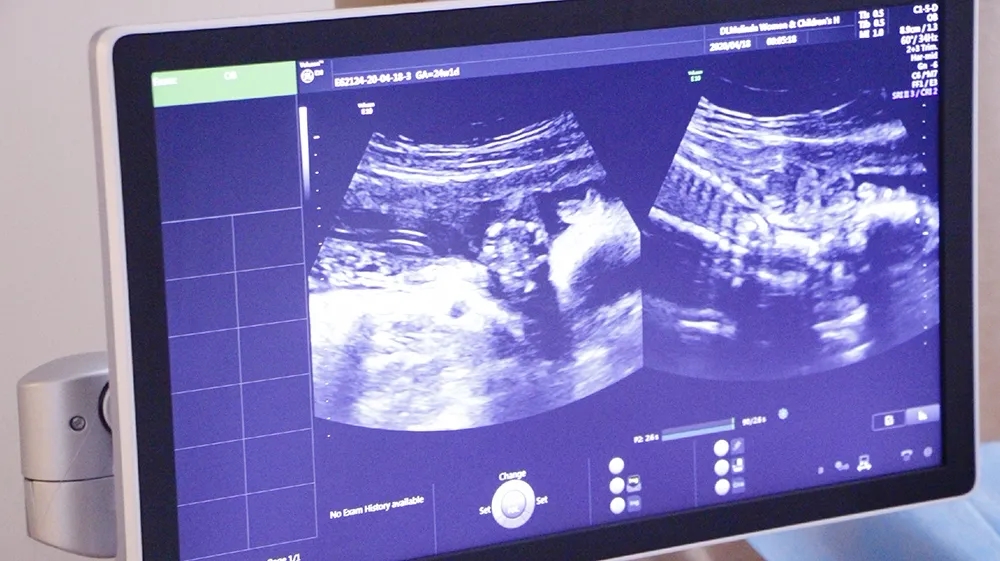

四维彩超是超声检查的一种,是孕期(zui)重要的一次超声检查,一般在孕24周进行,除了一般彩超的功能外,还可以进行胎儿头面部立体成像,可协助医生直接对胎儿先天畸形进行诊断,包括表面畸形、内脏畸形和头面部畸形,可实时观察胎儿动态的活动图像。

引进美国进口系列设备-清晰动态记录胎宝美琳达超声科引进多台美国GE-E10、美国GE-E8等系列机器。能够提高细节分辨率,实现在扫描同时即刻呈现胎儿标准生长曲线和相应测量数据。满足从早孕期研究到复杂胎心的全程早期检查和诊断,通过四维立体成像,清晰并动态记录宝宝在子宫内的活动和成长历程。